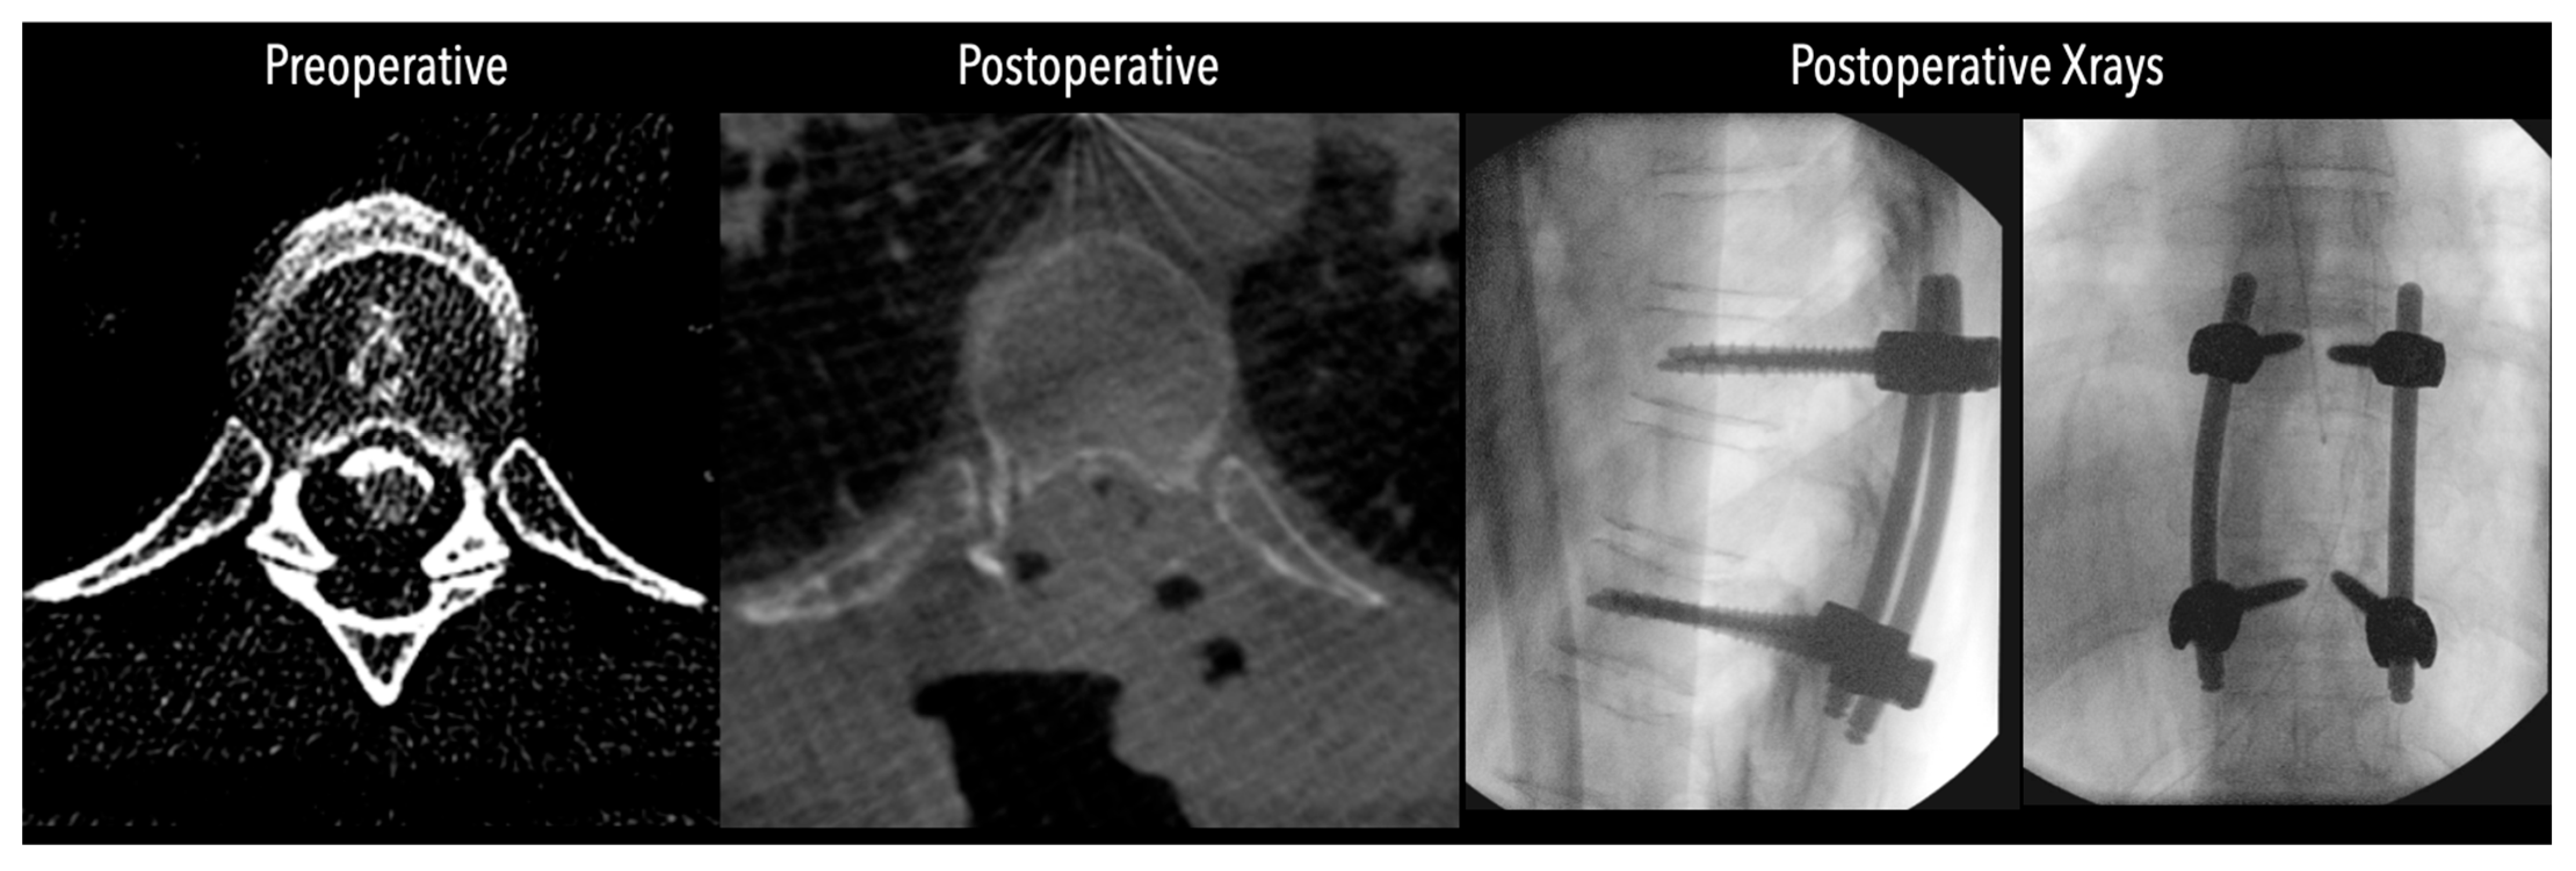

Figure 4. Comparative pre- and postoperative CT scans for two different patients (left and right), illustrating complete discectomy.

Figure 5. Left side: Comparative pre- and postoperative CT scan of a patient, illustrating complete discectomy. Right side: Postoperative X-rays illustrating fixation.

Figure 6. Left side: Comparative pre- and postoperative CT scan of a patient (axial views), illustrating complete discectomy.

In three of the seven cases, the exiting nerve root at the level of the herniation was ligated due to poor visualization and transected extradurally to improve access. In the remaining four patients, the nerve root was either preserved or dissected intradurally using isocool bipolar diathermy and microsurgical scissors. With gentle medial retraction of the cord under gravity and protection using a micro-patty, the calcified disc was exposed. The ventral dura, when intact, was incised sharply and dissected from the disc surface where possible (Figure 2a,b and Figure 3). Disc removal was performed using a hockey-stick-shaped Misonix bone scalpel with constant irrigation, guided by intraoperative neuronavigation. The disc material was resected to a depth of 1–2 mm beyond the posterior vertebral wall to ensure adequate decompression. A second O-Arm spin was routinely performed following discectomy to confirm satisfactory decompression, especially given the limitations of the postoperative MRI due to the metal artefact (Figure 4, Figure 5 and Figure 6).